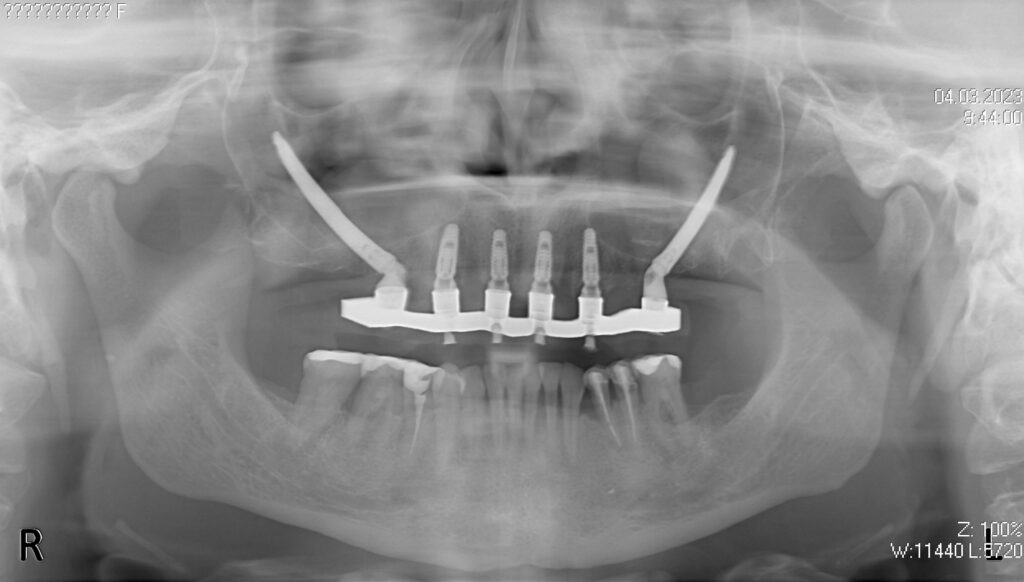

процесс работы

Что было сделано:

На верхней челюсти были удалены зубы, которые находились в неудовлетворительном состоянии, проведена комплексная имплантация по системе All-on-6, установлены 4 имплантата Megagen AnyOne и 2 скуловых имплантата NeoDent.

Спустя 7 дней на верхней челюсти зафиксирован металлоакриловый протез из 12 зубов.

снимок

работы врача